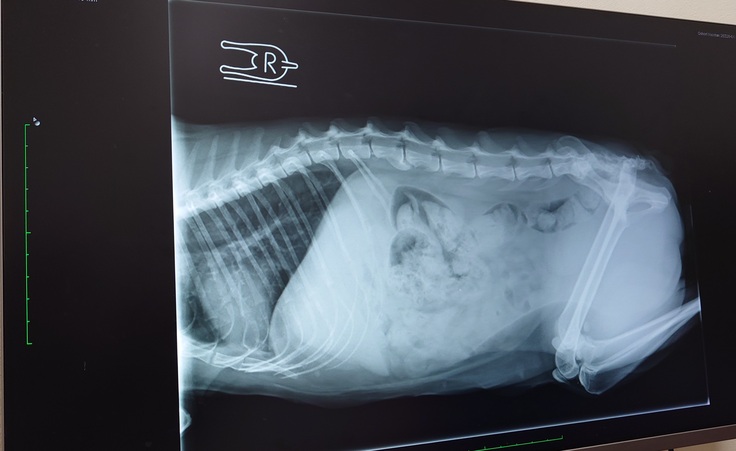

🐈レントゲン検査の結果、背骨に2つ奇形があることが分かりました。うんちの出が悪くて便秘気味になってるのもそれが原因かもとの事でした🐈

うんちもお腹の中にたくさん残ってるんだけど、ヨッちゃんの背骨に奇形が2つあるから、馬尾(ばび)症候群のような症状があって排便する時に痛みや違和感がある等でうまく力めてないのかもしれないということでした。